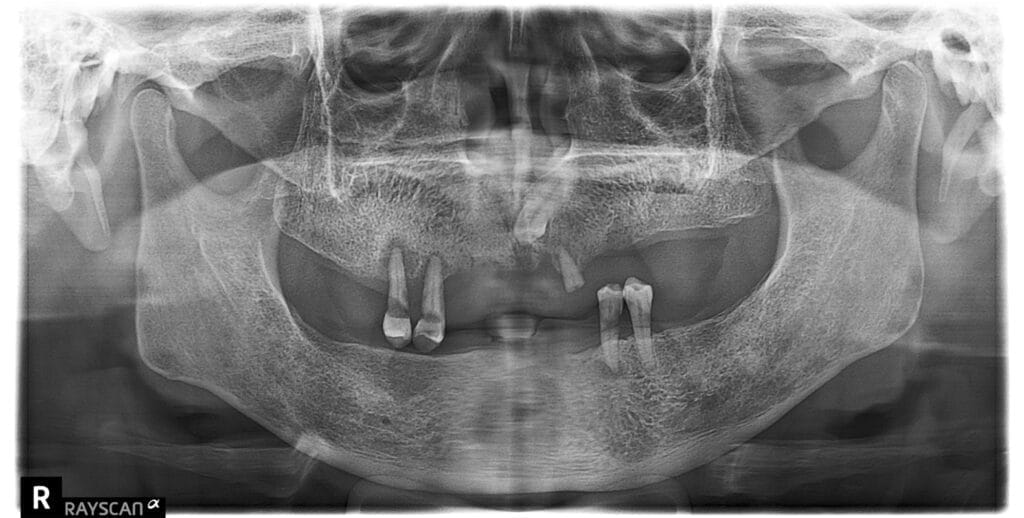

重獲新生系列②|告別活動假牙束縛,全口重建一次蛻變 發佈留言 / All-on-4/6速定植牙 / admin 66歲S先生原先長期使用活動假牙,進食常覺得不方便,配戴舒適度也不好,後來因牙周病的狀況,逐年導致缺牙越來越多 重獲新生系列②|告別活動假牙束縛,全口重建一次蛻變 閱讀全文 »

半固定式活動假牙 發佈留言 / 半固定式活動假牙 / admin 口腔缺牙多不方便吃東西,因此希望尋求全口重建的方式 口腔因缺牙過多無法正常吃東西,且因缺牙容易造成牙齦萎縮,剩 半固定式活動假牙 閱讀全文 »